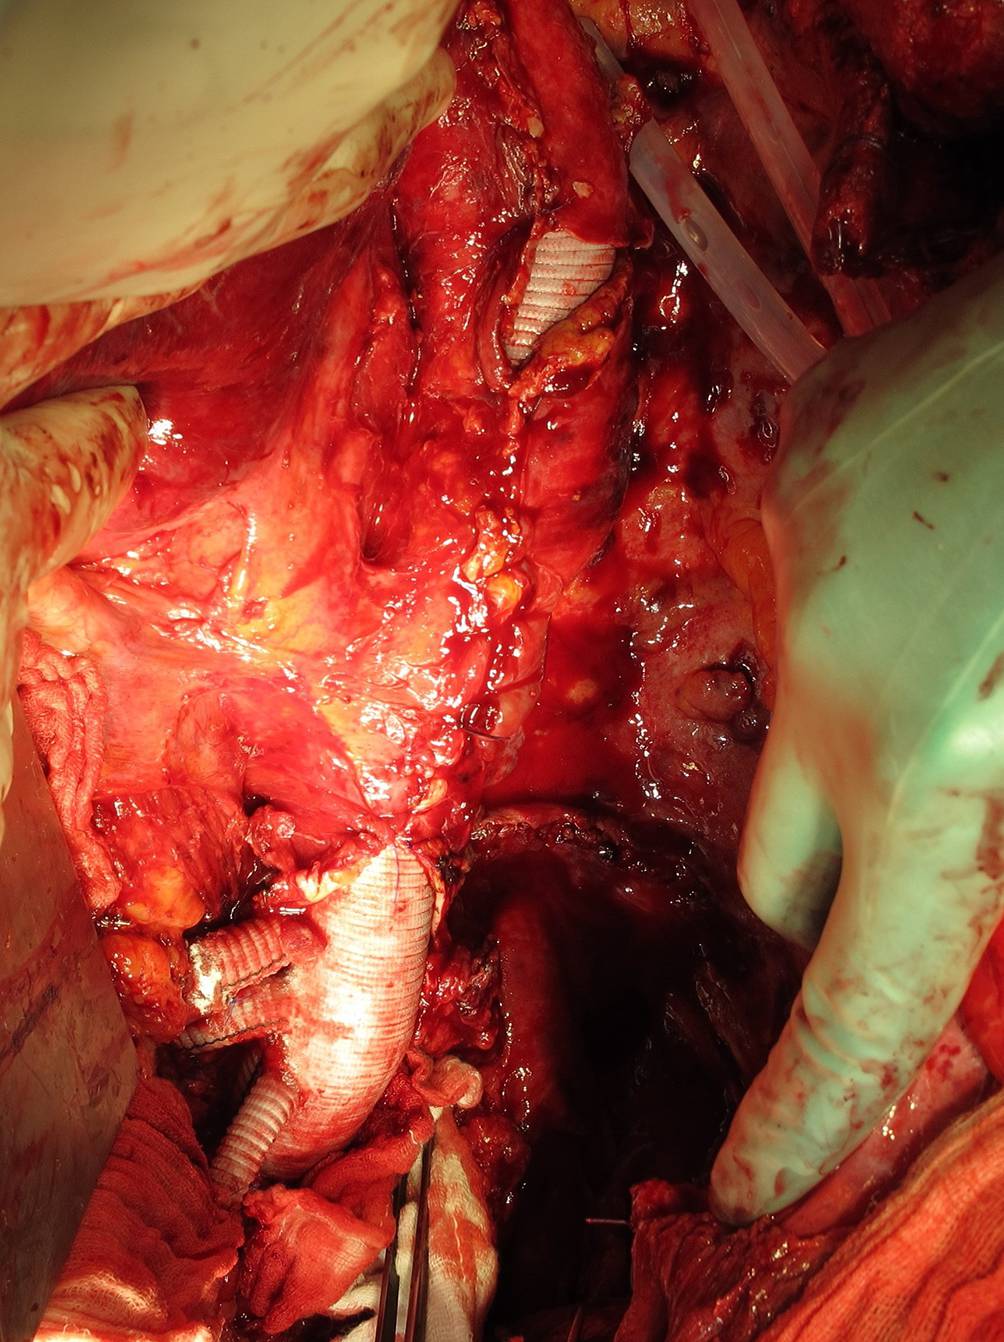

Linksherzbypass

Mithilfe des LHB wird das vom Patienten selbst oxygenierte Blut vom linken Vorhof ins arterielle System distal der Aortenquerklemmung gebracht. Das System wird durch eine Zentrifugalpumpe angetrieben und hat im Gegensatz zur HLM keinen Oxygenator. Der Vorteil des LHB ist die niedrigere Heparindosis, die im Vergleich zur HLM gegeben werden muss. Dies ist durch die geringere Fremdoberfläche, v. a. durch Verzicht auf einen Oxygenator, bedingt. Somit reicht üblicherweise eine Ziel-ACT von 200–300 s aus [3]. Die Kanülierung für den LHB erfolgt im Bereich der linken unteren Lungenvene (Abb. 4). Der Rückstrom des Blutes erfolgt aortal. Der Entzug von Blut aus der Lunge ist auch protektiv in punkto Lungenödem. Ein potenzieller Nachteil ist das Risiko einer Nachblutung aus diesem Bereich. Der Nachteil ist, dass kein Maschinensauger vorhanden ist, sodass hier primär mit dem Cellsaver-Sauger gearbeitet wird. Die Steuerung der Perfusion mit LHB erfolgt durch den Blutdruck der A.-radialis-Linie und der A.-femoralis-Drucklinie. Mit Steuerung der Umdrehungszahl der Zentrifugalpumpe und durch Katecholamingabe intravenös wird ein distaler Perfusionsdruck von 60–80 mm Hg aufrechterhalten.

Abb. 4

Kanülierung der Lungenvene für die Operation mit Linksherzbypass